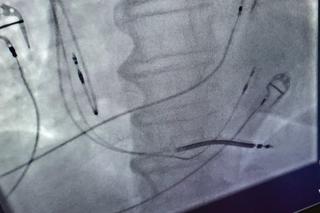

W Szpitalu Miejskim w Gliwicach przeprowadzono kolejny innowacyjny zabieg. Kardiolodzy wszczepili pacjentowi rozrusznik serca z najnowocześniejszym typem stymulacji.

Kolejny wyjątkowy zabieg w Szpitalu Miejskim nr 4 w Gliwicach. Po raz pierwszy w historii placówki lekarze wszczepili pacjentowi rozrusznik serca z najnowocześniejszym typem stymulacji. Innowacyjny zabieg wiąże się z wieloma korzyściami dla pacjenta.

- Wyjątkowość tego zabiegu polegała na tym, że wszczepiliśmy pacjentowi rozrusznik serca z najbardziej nowoczesnym typem stymulacji, gdyż była to stymulacja układu umożliwiającego wytwarzanie i przewodzenie impulsów elektrycznych generujących fizjologiczne skurcze przedsionków i komór - tłumaczyła dr Anna Szajerska-Kurasiewicz ze Szpitala Miejskiego nr 4 w Gliwicach.

Do tej pory lekarze szpitala wszczepiali elektrodę do koniuszka prawej komory, a tym razem umieścili ją w lewej odnodze pęczka Hisa. Powoduje to, że impuls w sercu rozchodzi się najbardziej fizjologiczną z możliwych dróg, co ma duże korzyści dla pacjenta. W odróżnieniu od pacjentów, którym wszczepiono zwykłe rozruszniki serca, zniwelowano ryzyko wystąpienia objawów kardiomiopatii postymulacyjnej, czyli uszkodzenia serca.